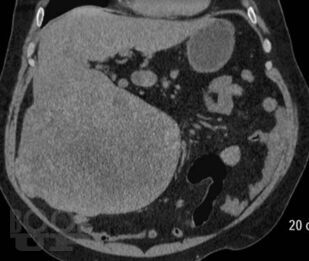

В книге приведены типичные клинико-рентгенологические ситуации, взятые авторами из повседневной практической работы в отделе лучевых методов диагностики и лечения Института хирургии им. А.В. Вишневского. Проанализированный материал охватывает хирургические заболевания органов брюшной полости и забрюшинного пространства вне острых или неотложных состояний. В первой части книги читателю предоставлена максимальная возможность сделать самостоятельное заключение о заболевании после анализа жалоб пациентов, анамнеза заболевания и приведенных изображений рентгеновских и КТ-исследований. Во второй части книги читатель может проверить правильность хода своих рассуждений и собственного заключения. Решение подобных ситуационных задач, несомненно, послужит большим подспорьем как начинающим, так и опытным врачам лучевой диагностики в их практической работе.